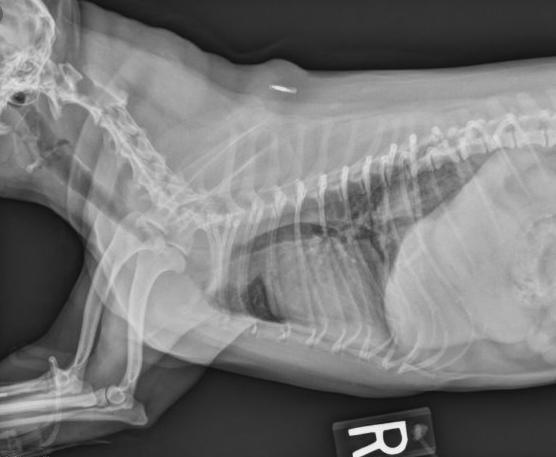

X光片是最常用的方法。主要拍颈部、胸部侧位、腹背位为主。如果在图像上看到气管变狭窄,则可以进行诊断。

但像X光片方法基本可以轻易看出问题在何处。

影像检查结果